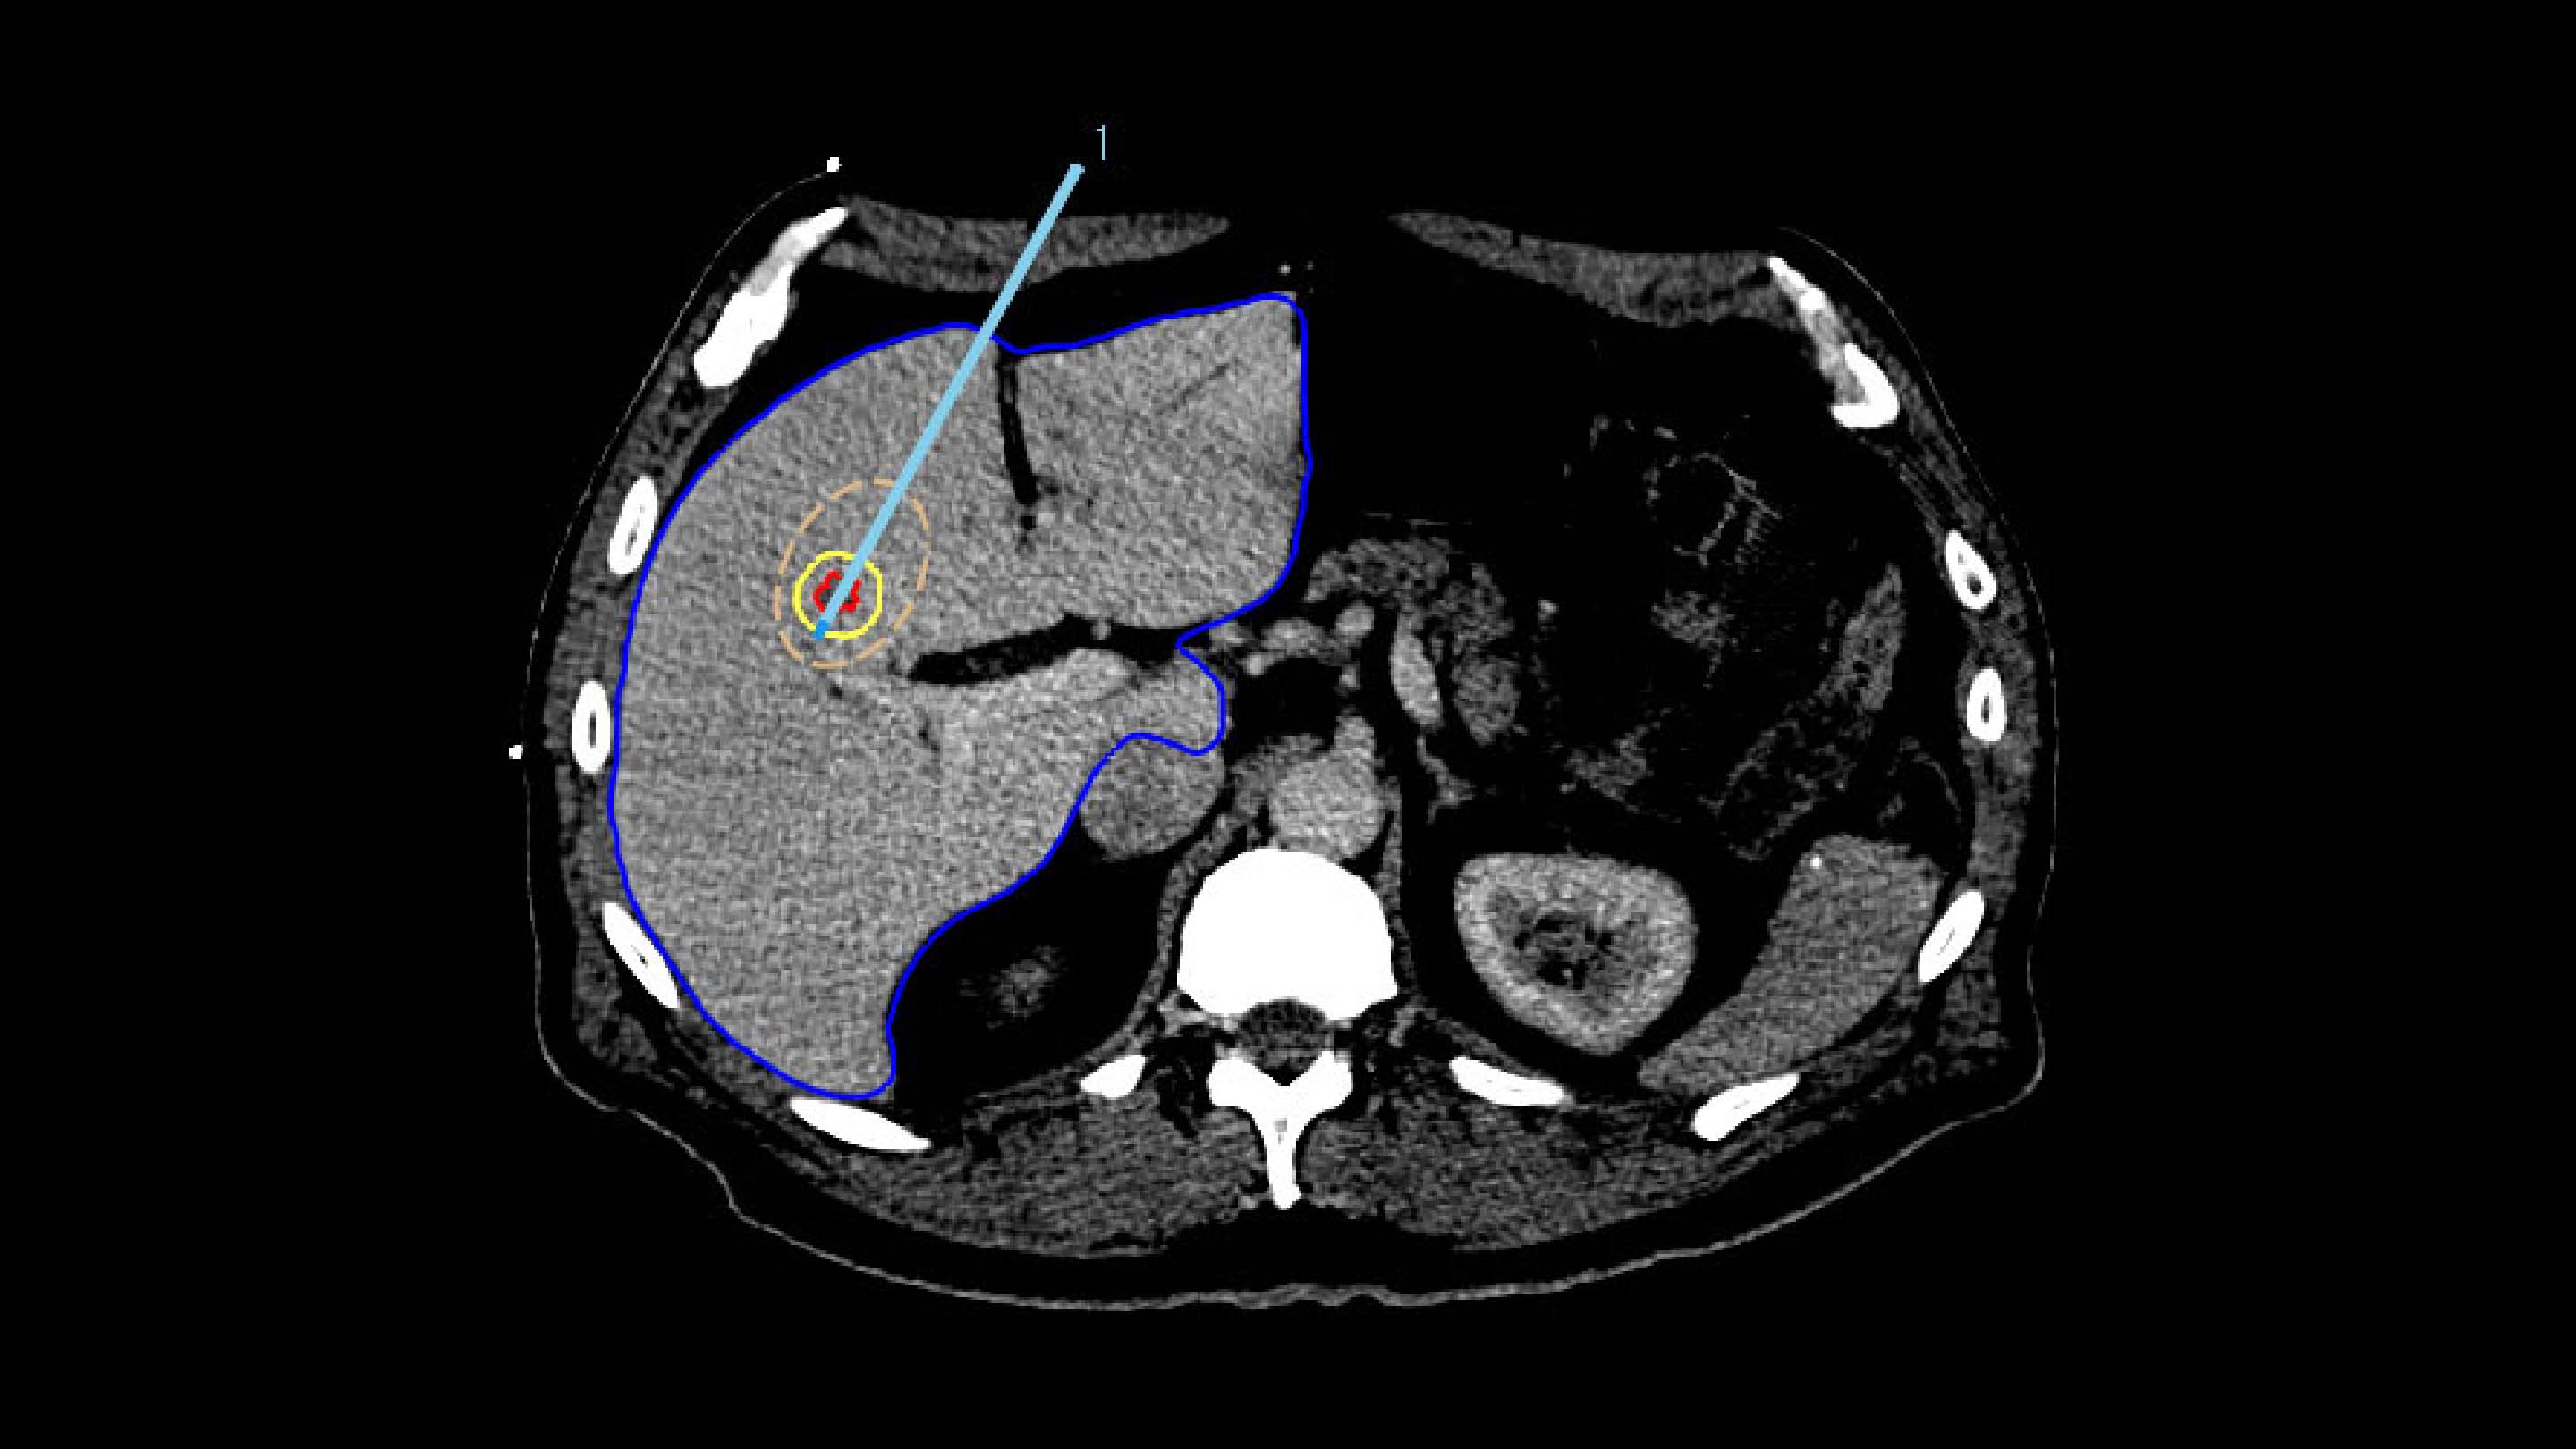

The Liver Ablation module offers tools for automatic segmentation of relevant structures. Combined with the ability to place virtual applicators and estimate the ablation zone, our software assists users to determine the optimal number of applicators and their precise placement.

2. TARGETING

To ensure accurate applicator placement before treatment, the segmented tumors from the planning phase are mapped using deformable registration, allowing for a visualization of the anticipated tumor position. Additionally, the ablation zone can be estimated based on the applicator parameters, such as its current position, selected power, and ablation duration.